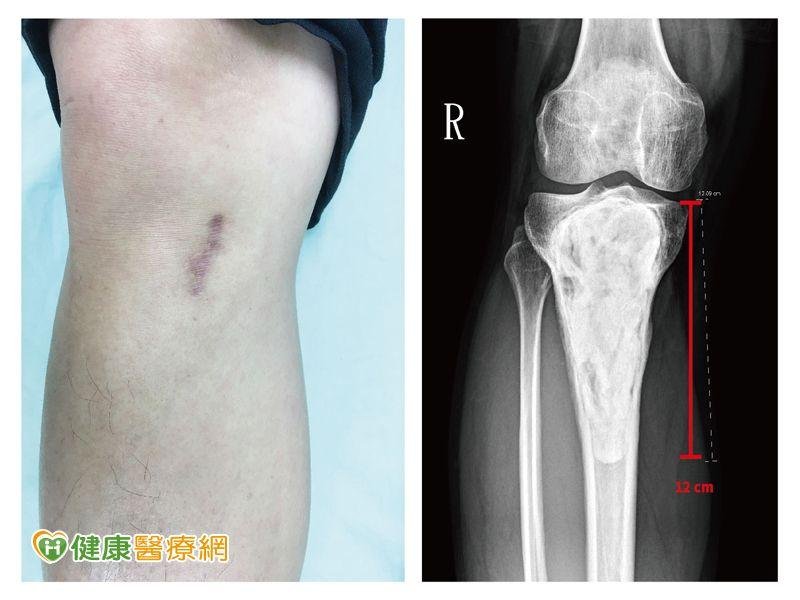

腳踝腫痛莫輕忽 恐因罕見骨腫瘤惹禍

20幾歲年輕人通常是體力最好的時候,相約打球、瘋路跑,運動傷害在所難免;但是要小心,若是有手腕、腳踝疼痛,可別輕忽,可能是罹患了骨科界少見的「骨巨大細胞瘤」!醫師提醒,骨巨大細胞瘤常發生於20-40歲年輕族群,雖然為良性腫瘤,但腫瘤不但復發率高,也有轉移的風險,若不積極治療,輕則造成患部的腫